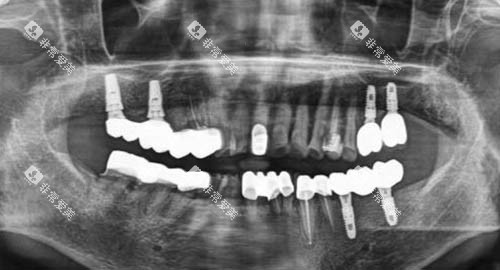

如智能化口腔全景机,能够快速、比较准地获取口腔超全影像,为医生的诊断提供清晰、详细的依据;靠前的种植牙系统,确保种植牙手术的更准一些性和可靠性;舒适的牙科综合治疗椅,让患者在治疗过程中感受到更多的舒适和便利。

在种植牙领域,医院的医生凭借过关的技术和丰富的经验,成功为众多缺牙患者种上了新牙,修养了患者的咀嚼功能和美观。